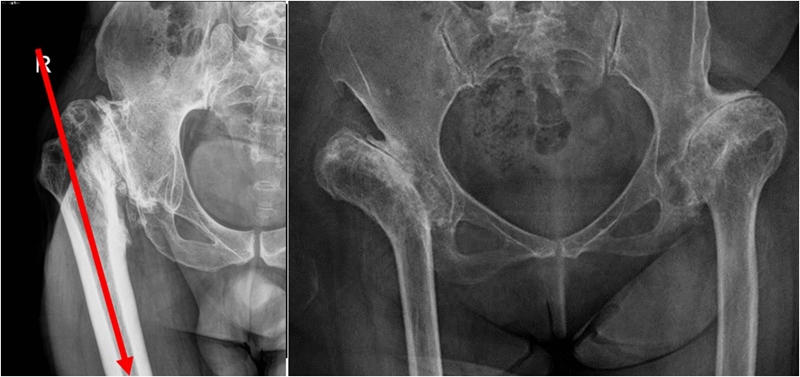

Ⅲ、干骺端畸形

硬化骨、骨赘、骨质疏松、髓腔宽大

转子间骨折畸形愈合后常导致干骺端畸形,干骺端遗留大量硬化骨或髓腔成角,术中需在确认髓腔开口位置后,首选用小骨刀或高速磨钻去除硬化骨,打通髓腔。

干骺端畸形还可引起髓腔增宽,骨量减少,骨质疏松,不能为近端压配固定型的假体提供良好稳定。宜选用全微孔涂层远端固定假体。

(3)股骨成角畸形

程度轻,且远离假体安放位置:近端固定短柄假体或小号骨水泥型假体。

严重且靠近假体安放位置:必须行截骨矫正,以获得良好的对线。